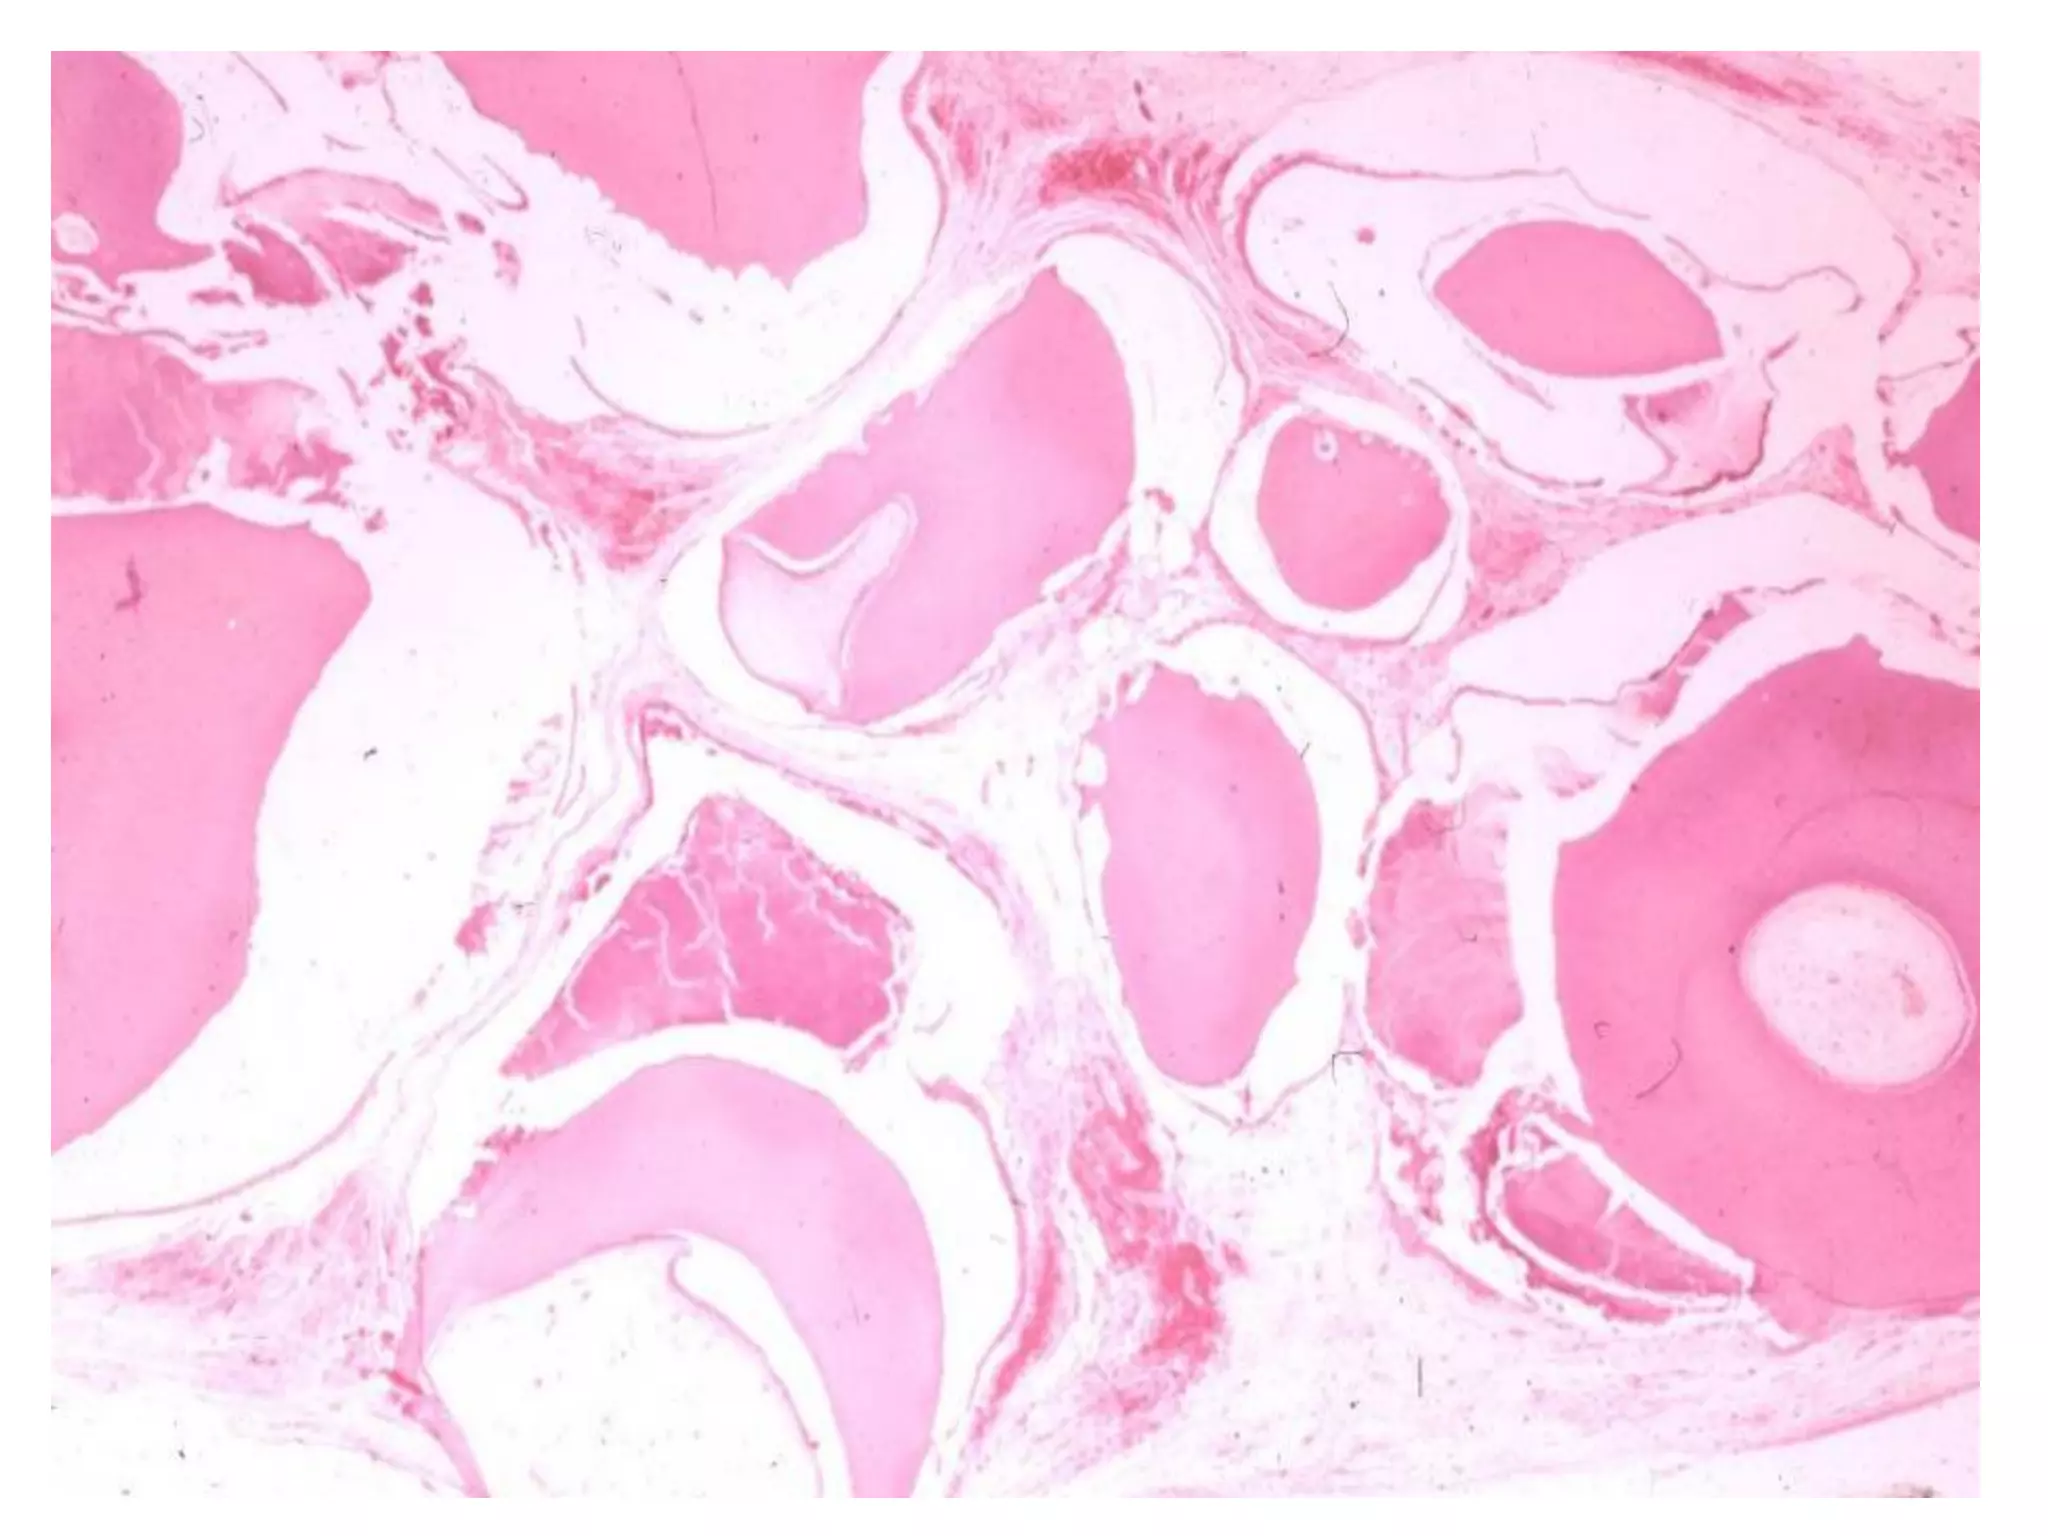

Giaûi phaãu beänh

 Coù nhieàu döôùi típ (subtypes) treân vi theå nhöng

chuùng thöôøng mang ít ñaëc tính cuûa khoái u.

 Thöôøng gaëp nhaát laø daïng nang (follicular type) vaø

daïng ñaùm roái (plexiform type).

 U men ñaëc daïng nang goàm caùc ñaûo teá baøo bieåu moâ

gioáng cô quan men naèm trong moâ lieân keát sôïi tröôûng

thaønh.

 U men ñaëc daïng ñaùm roái goàm caùc daây (cords) bieåu

moâ taïo raêng daøi thoâng nhau hoaëc caùc laù (sheets)

bieåu moâ lôùn hôn. Moâ ñeäm loûng leõo vaø nhieàu maïch

maùu hôn.

Giaûi phaãu beänh:

 Goàm toå chöùc trung moâ giaøu teá baøo gioáng nhuù

raêng nguyeân thuûy laãn vôùi bieåu moâ taïo raêng

ñang taêng sinh.